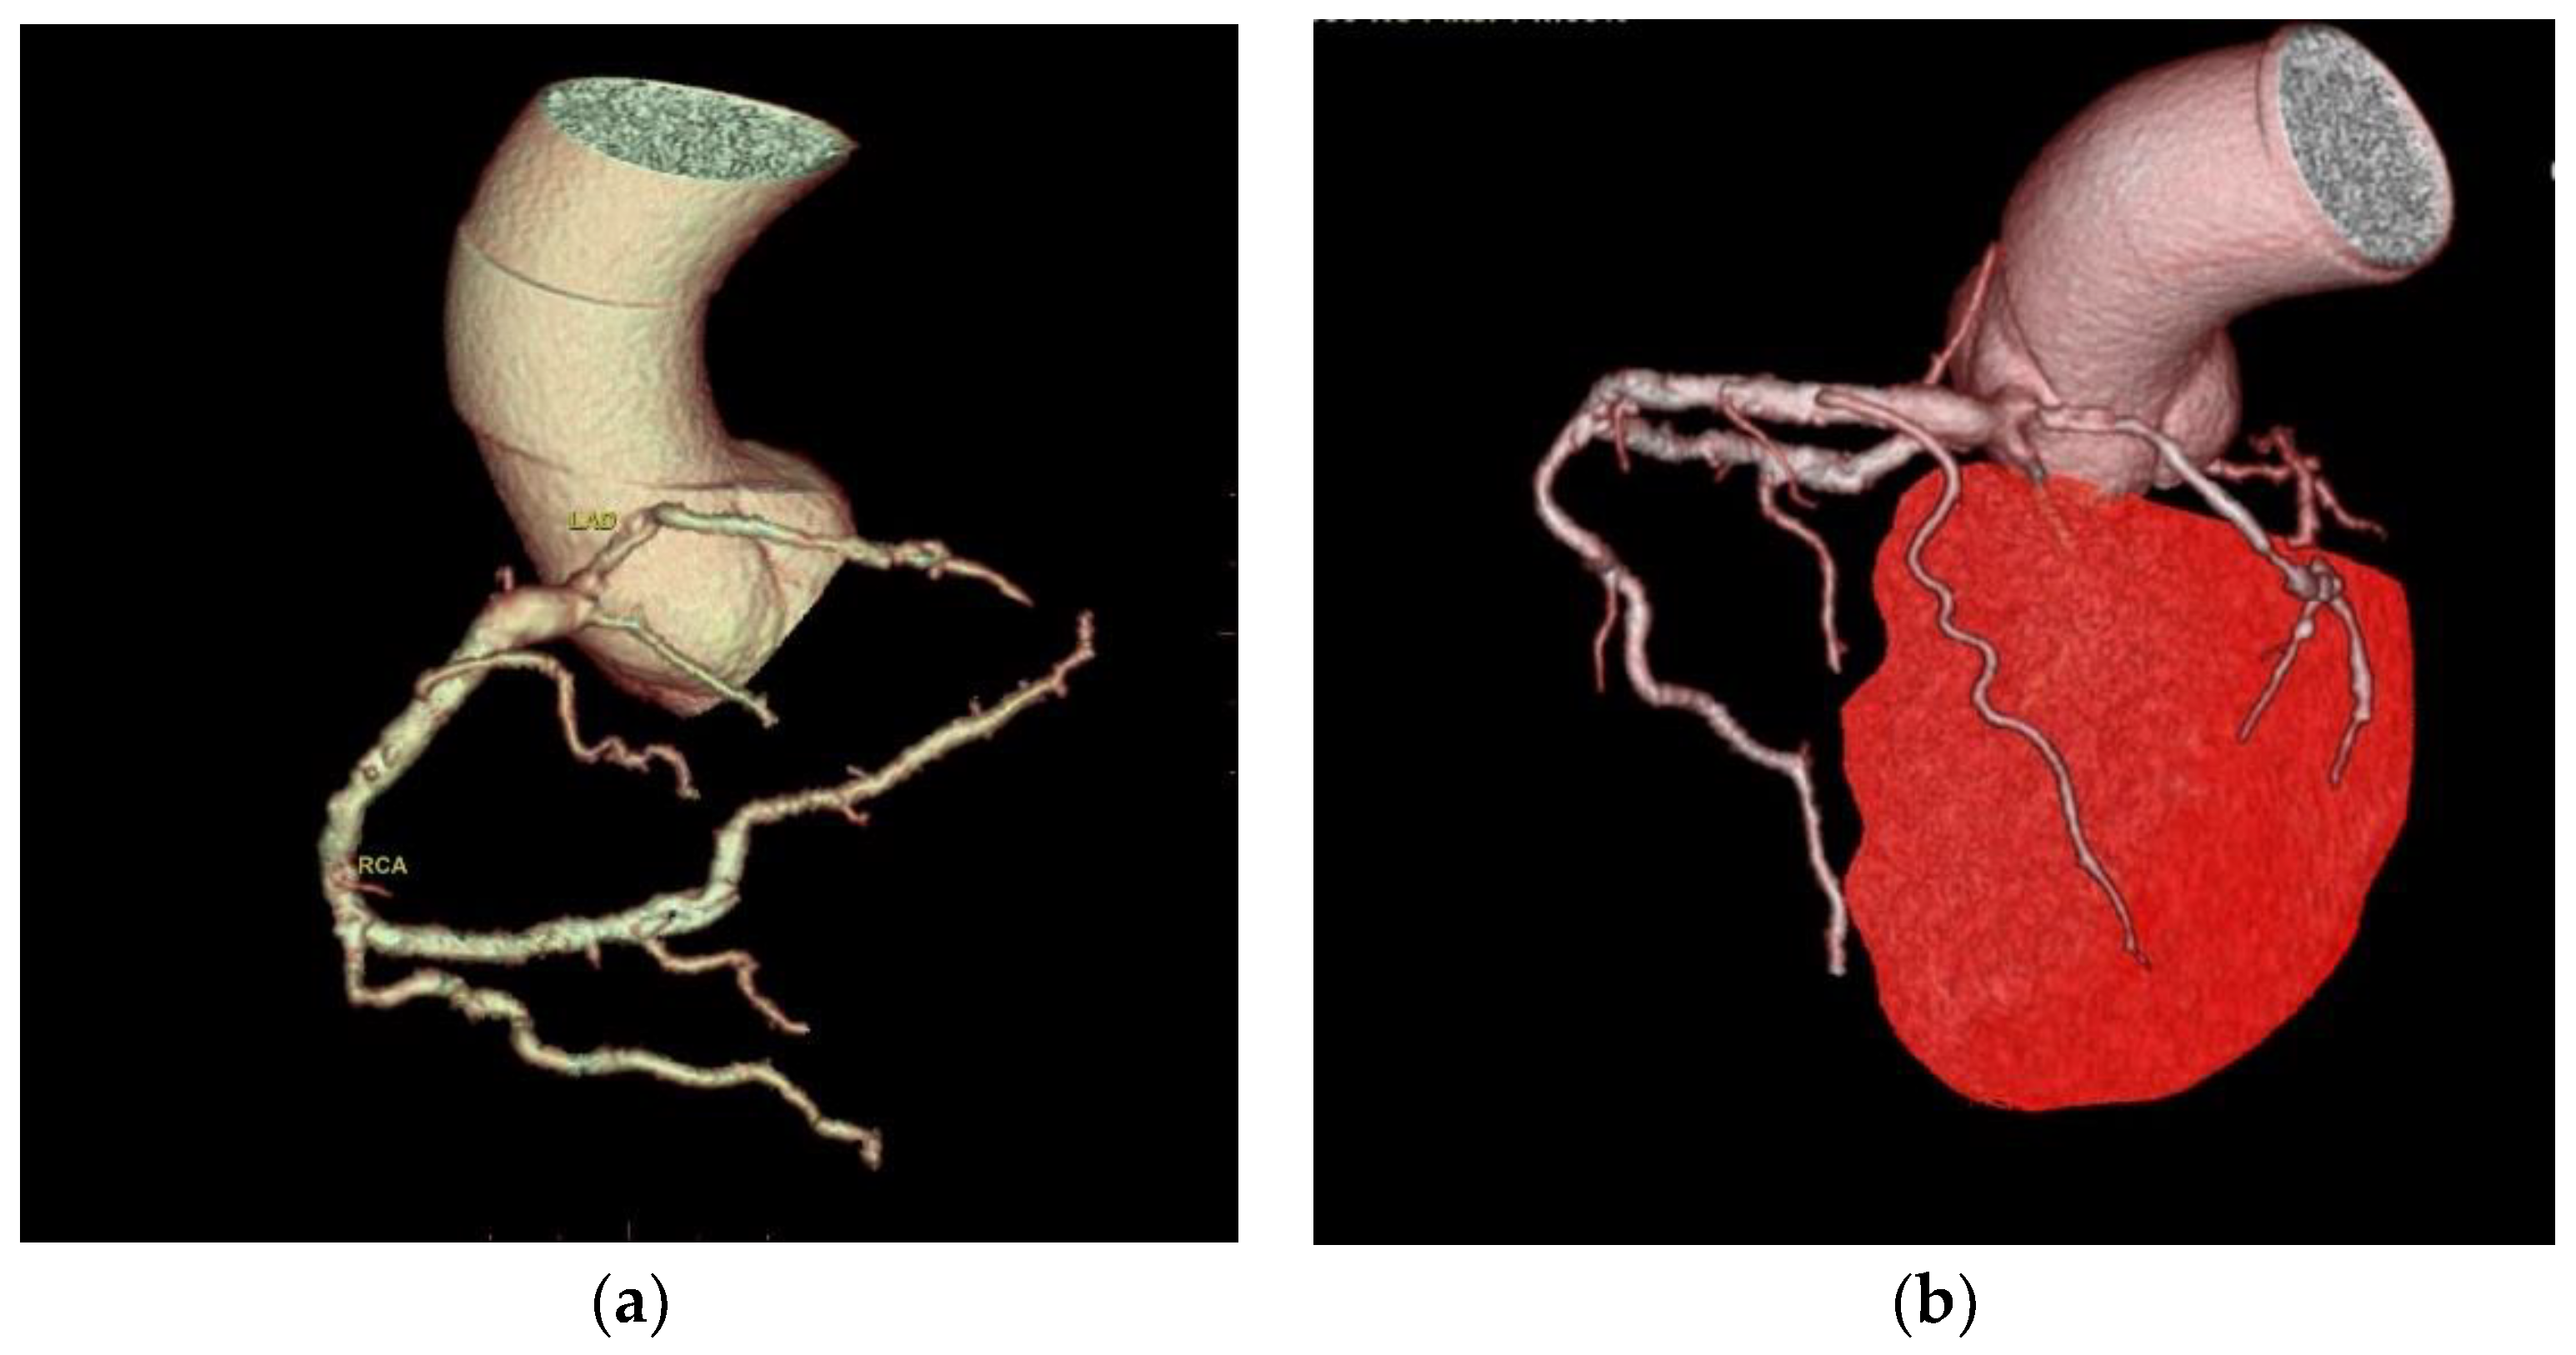

Two cases of anomalous origin of the left main coronary artery arising from the right sinus were found, as depicted in

Figure 1.

Two cases of a left coronary artery originating from the right coronary sinus were found; this is a rare anomaly; the prevalence of coronary artery anomalies arising from the opposite site in the scientific literature is between 0.1% and 0.2%, with the left coronary arising from the right sinus being six times rarer than the right coronary artery originating from the left sinus [

19]. This is considered an anomaly associated with a risk of sudden death estimated between 0.17% and 0.35% because of the larger myocardial territory associated with ischemic risk [

19,

20].